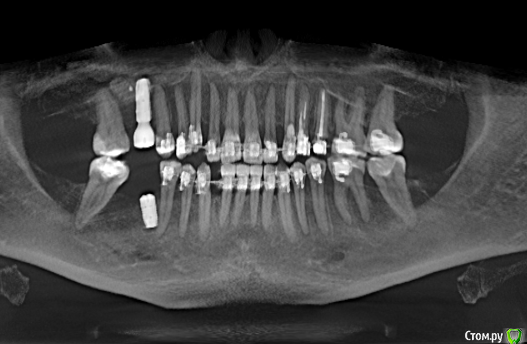

Тата Богачевская Опубликовано 24 октября, 2020 Поделиться Опубликовано 24 октября, 2020 Здравствуйте. Меньше месяца назад на место отсутствующего 46 зуба мне был установлен имплантат с расщеплением альвеолярного гребня. Операция прошла хорошо, никаких осложнений. В настоящий момент ничего не беспокоит. Тем не менее положение имплантата у меня вызывает беспокойство - слишком близко к корню 45 зуба и под углом к нему. Однако доктор уверяет, что положение имплантата нормальное, не идеальное конечно, но не критичное. Скажите, пожалуйста, угрожает ли такое положение имплантата 45 зубу, возможно ли будет в дальнейшем установить коронку в правильное положение? Или нужно удалить имплантат? Благодарю.https://yadi.sk/d/Tzd1aKb84eU3wQ Ссылка на комментарий

It'sGeorgy Опубликовано 24 октября, 2020 Поделиться Опубликовано 24 октября, 2020 Попробуйте перезалить КТ. Открывается не полностью, только панорамный вид.Если судить по панорамному виду, имплантат лучше переустановить. Ссылка на комментарий

red_butler Опубликовано 25 октября, 2020 Поделиться Опубликовано 25 октября, 2020 Имплант нужно переставить Ссылка на комментарий

колесников Опубликовано 25 октября, 2020 Поделиться Опубликовано 25 октября, 2020 4 месяцаИмплант 46 нужно убрать. Зуб 47ой дистализировать ортодонтически. Переустановить имплант 46 в правильной ортопедической позиции с десневой пластикой. К окончанию лечения вероятно будут вопросы к импланту 16,положение его платформы не самое оптимальное . 1 Ссылка на комментарий

колесников Опубликовано 25 октября, 2020 Поделиться Опубликовано 25 октября, 2020 (изменено) Поясните пожалуйста понятным для пациента языком, что значит "положение платформы 16 имплантата не самое оптимальное" .Я только на панорамный снимок ориентируюсь,возможно все не так как кажется. Мне представляется так:чтобы поставить клык (13) в зубной ряд,надо дистализировать 15,14 ,что создаст проблем для протезирования 16,который уже сейчас близко к 15 ,для моделирования коронки моляра 16. Вначале ортодонтия,после имплантация. Немного поторопились с имплантами. Или придётся удалить 15,чтобы не трогать имплант 16 Изменено 25 октября, 2020 пользователем колесников Ссылка на комментарий